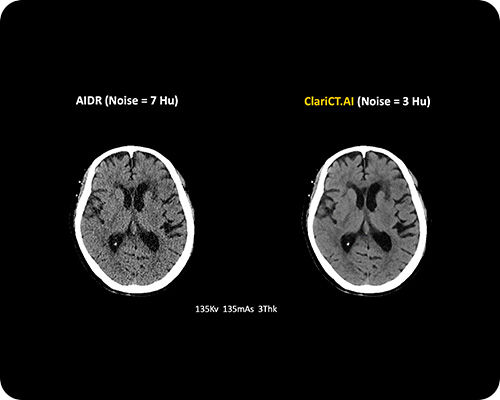

ClariCT.AI

AI-Powered Radiation Reduction

The first AI software that dramatically reduces radiation exposure while delivering the highest quality CT images using advanced AI denoising technology.

Reduces radiation exposure by 70-95% while maintaining superior image quality